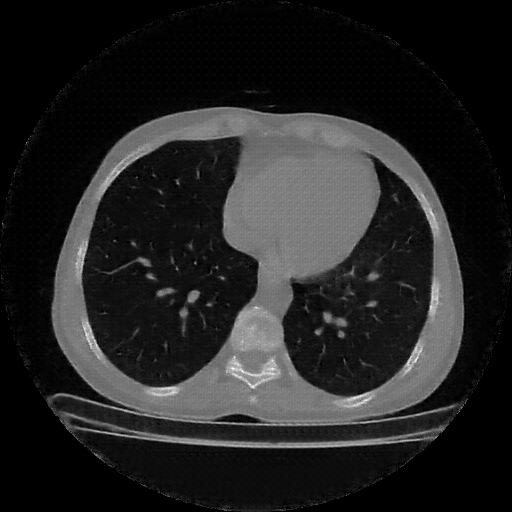

Reconstructed NATIVE CT scan (cycle consistency)

Full window (WL 1023.5, WW 4095 β†’ Low βˆ’1024, High +3071)

Actual HU range: [-1024.0, 1095.7]

Lung window (WL -600, WW 1500 β†’ Low βˆ’1350, High +150)

Actual HU range: [-1350.0, 150.0]